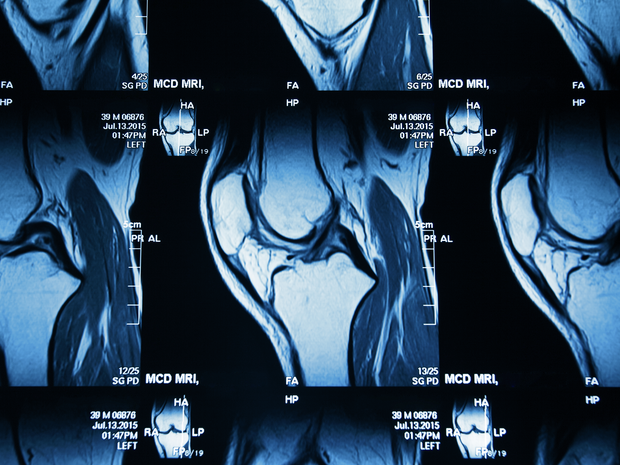

First, your surgeon will obtain x-rays to evaluate your joint and determine whether or not you're a candidate for cartilage restoration surgery. Advanced imaging, such as an MRI, is usually necessary to assess cartilage defects and develop a treatment plan.